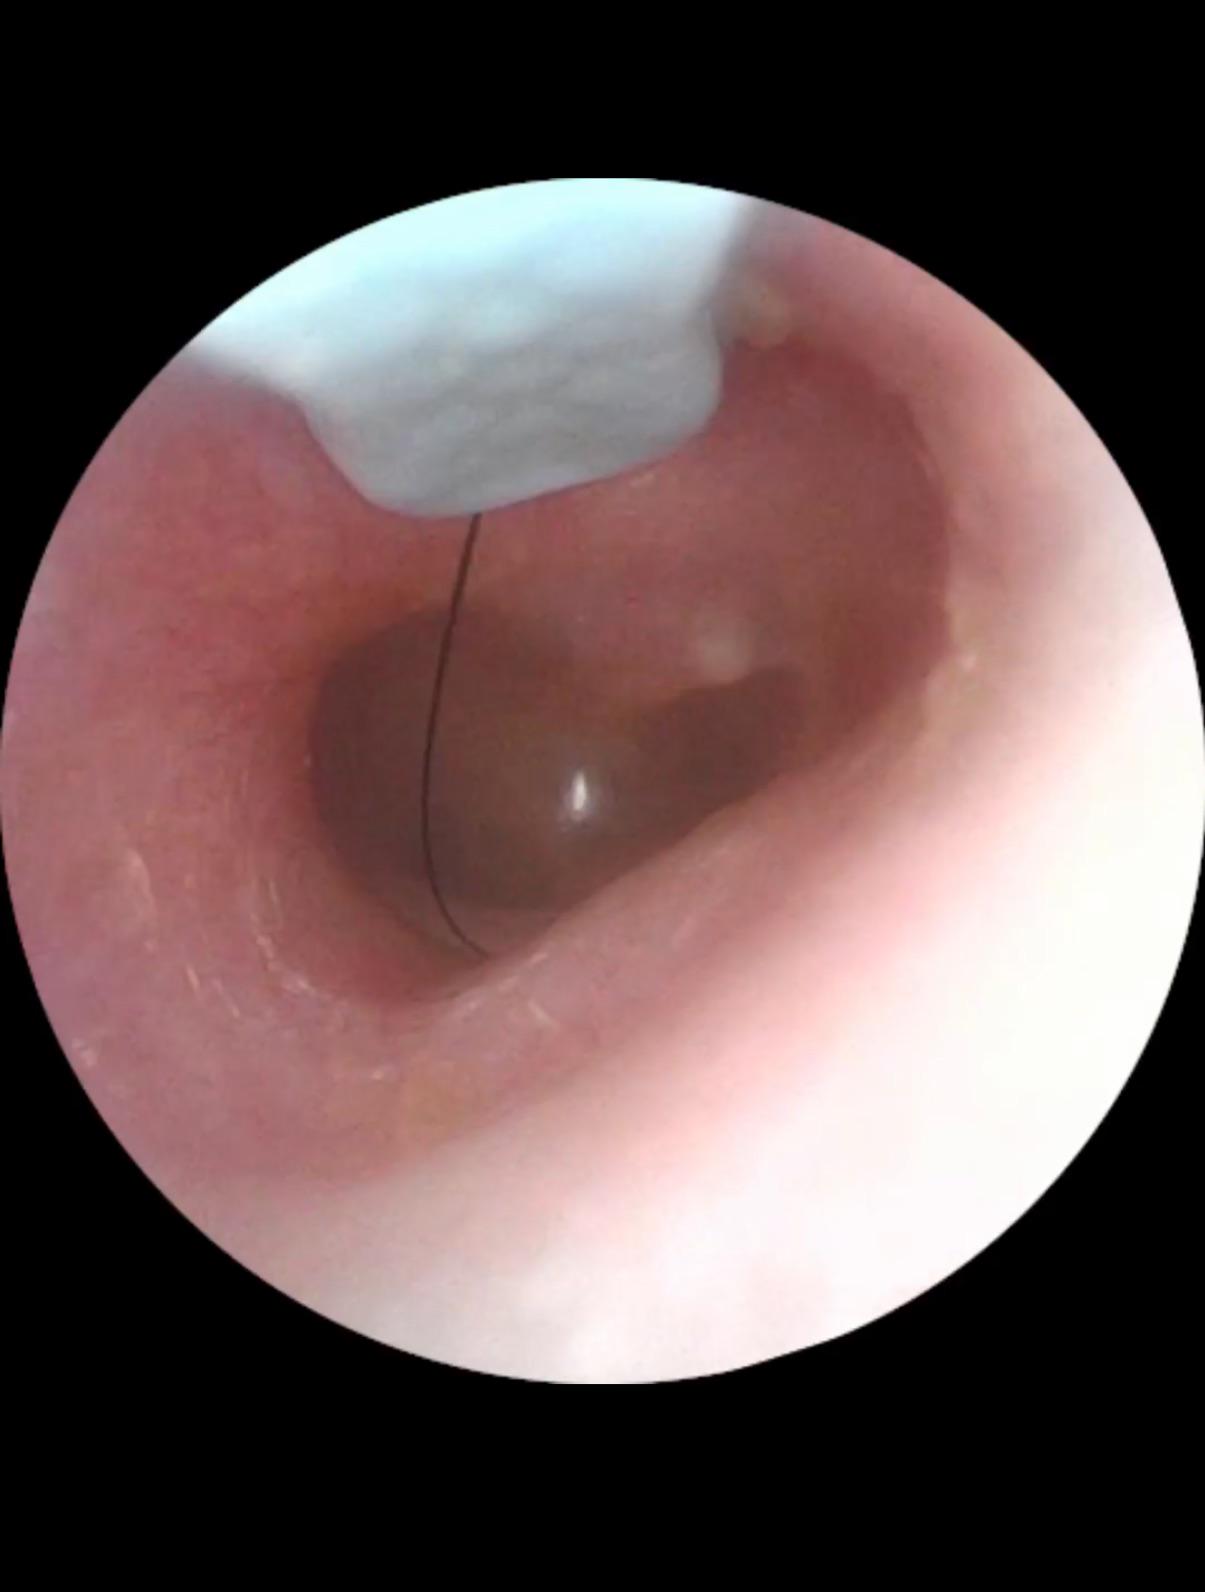

dog hair stuck behind ear is driving me crazy with ringing in the ear